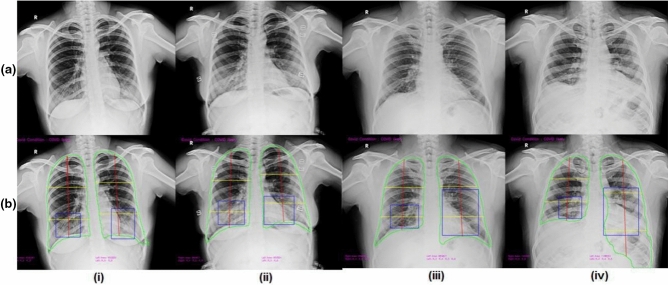

Figure 4.

Table 1 depicts the performance metrics of the CovBaseAI model on different independent validation datasets. Since the ground truth available for the validation dataset was either positive or negative (i.e. RT-PCR +ve/−ve or consolidation +ve/−ve) and the output of the CovBaseAI model is given in three classes (COVID likely, COVID indeterminate and COVID unlikely), the COVID indeterminate class was merged with COVID likely class for calculating performance metrics such as Sensitivity, Specificity, Accuracy, Negative Predictive Value (NPV), etc. Figure 5 depicts the sample of True positive, False positive, True Negative, and False Negative obtained by the CovBaseAI model. Validation studies corresponding to the CovBaseAI model were done using CARPL. Figure 6 shows bounding boxes of representative false-positive images from IITAC1.4K data that were read as normal by the radiologist. On review, the findings inside these bounding boxes were prominent bronchovascular markings, a common finding in the Indian subcontinent, with no clinical significance. Table 2 shows the concordance of bounding boxes (mAP) between lesions identified by AI and radiologists. In 905 CxRs (434 RT-PCR +ve and 471 historical scans) from Independent Validation datasets, read by four radiologists, intersections between AI-human pairs are like human–human pairs. Further, in the case of the IITAC1.4k dataset, which is read by a single radiologist, the majority of the time the bounding box of AI and radiologist had an intersection. Thus, the determination of COVID-19 pneumonia in our model is based on the same parts of the CxR as marked by the expert radiologist. Therefore, the explainability can be considered to be high.

Figure 5.

Samples of true positive, false positive, true negative, and false negative from independent validation set of 905 CxRs (a) Ground truth CxR (b) CovBaseAI inferencing result.

Figure 6.

Samples of false-positive from IITAC1.4K dataset (a) Ground truth CxR (b) CovBaseAI inferencing result.